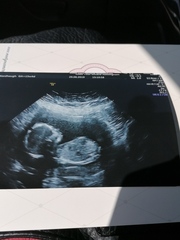

First post but I've been reading for a while!

I'm 16 weeks and had a private scan today that told us we're having a girl! This is our second, was lovely having our (almost) three year old son with us at the scan Smile